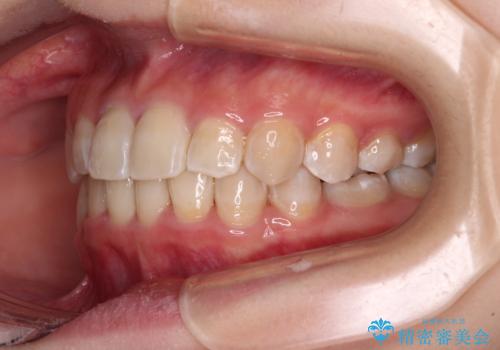

- 犬歯のクロスバイトを気にして来院された患者様です。

マウスピース矯正とワイヤー矯正の両方を提案しましたが、インビザラインの自己管理が煩わしいとのことで、ワイヤー装置による矯正治療を行うこととしました。

犬歯は歯根が太くて長いため、クロスバイトを改善するのは大変であることが多いですが、比較的スムーズに改善することができました。

インビザラインであったら、もっと期間はかかっていたような印象です。